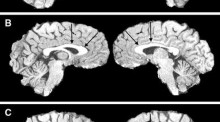

Equations to describe brain size across the continuum of human lifespan Matthew BorzageStefan BlümlIstvan Seri Original Article 14 December 2012 Pages: 141 - 150